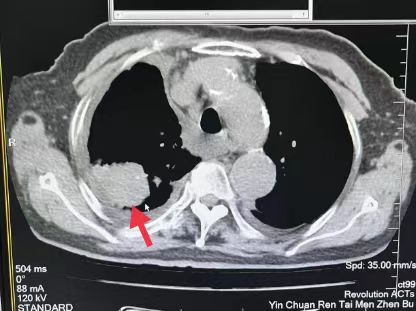

03、**女士,69岁

于2023年10月17日在邯郸仁泰东区体检,低剂量肺部螺旋CT检查提示:右侧上纵隔椎体旁占位病变26*38mm。2023年10月18通知客户到三甲医院进一步检查。2023年11月18日跟踪回访,客户反馈已在北京肿瘤医院完成手术,术后恢复良好。